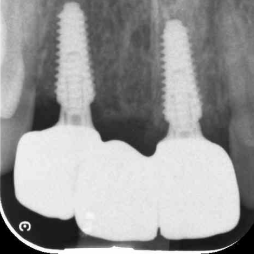

Transformations

Dental Implants closely mimic natural teeth in both appearance and function. They are exceptionally durable and can last a lifetime with proper care.